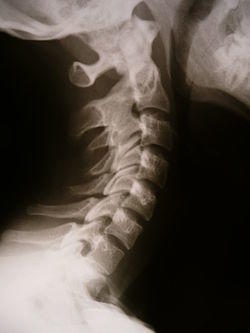

Radiology 1300594 Nevit.jpg

X-ray showing synostosis in the cervical spine